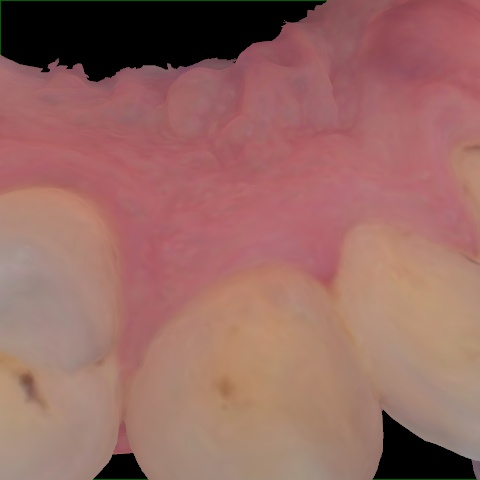

Image 1991 / 2000

NHD39969

Annotated as "Good"

Original Image Rendering Image